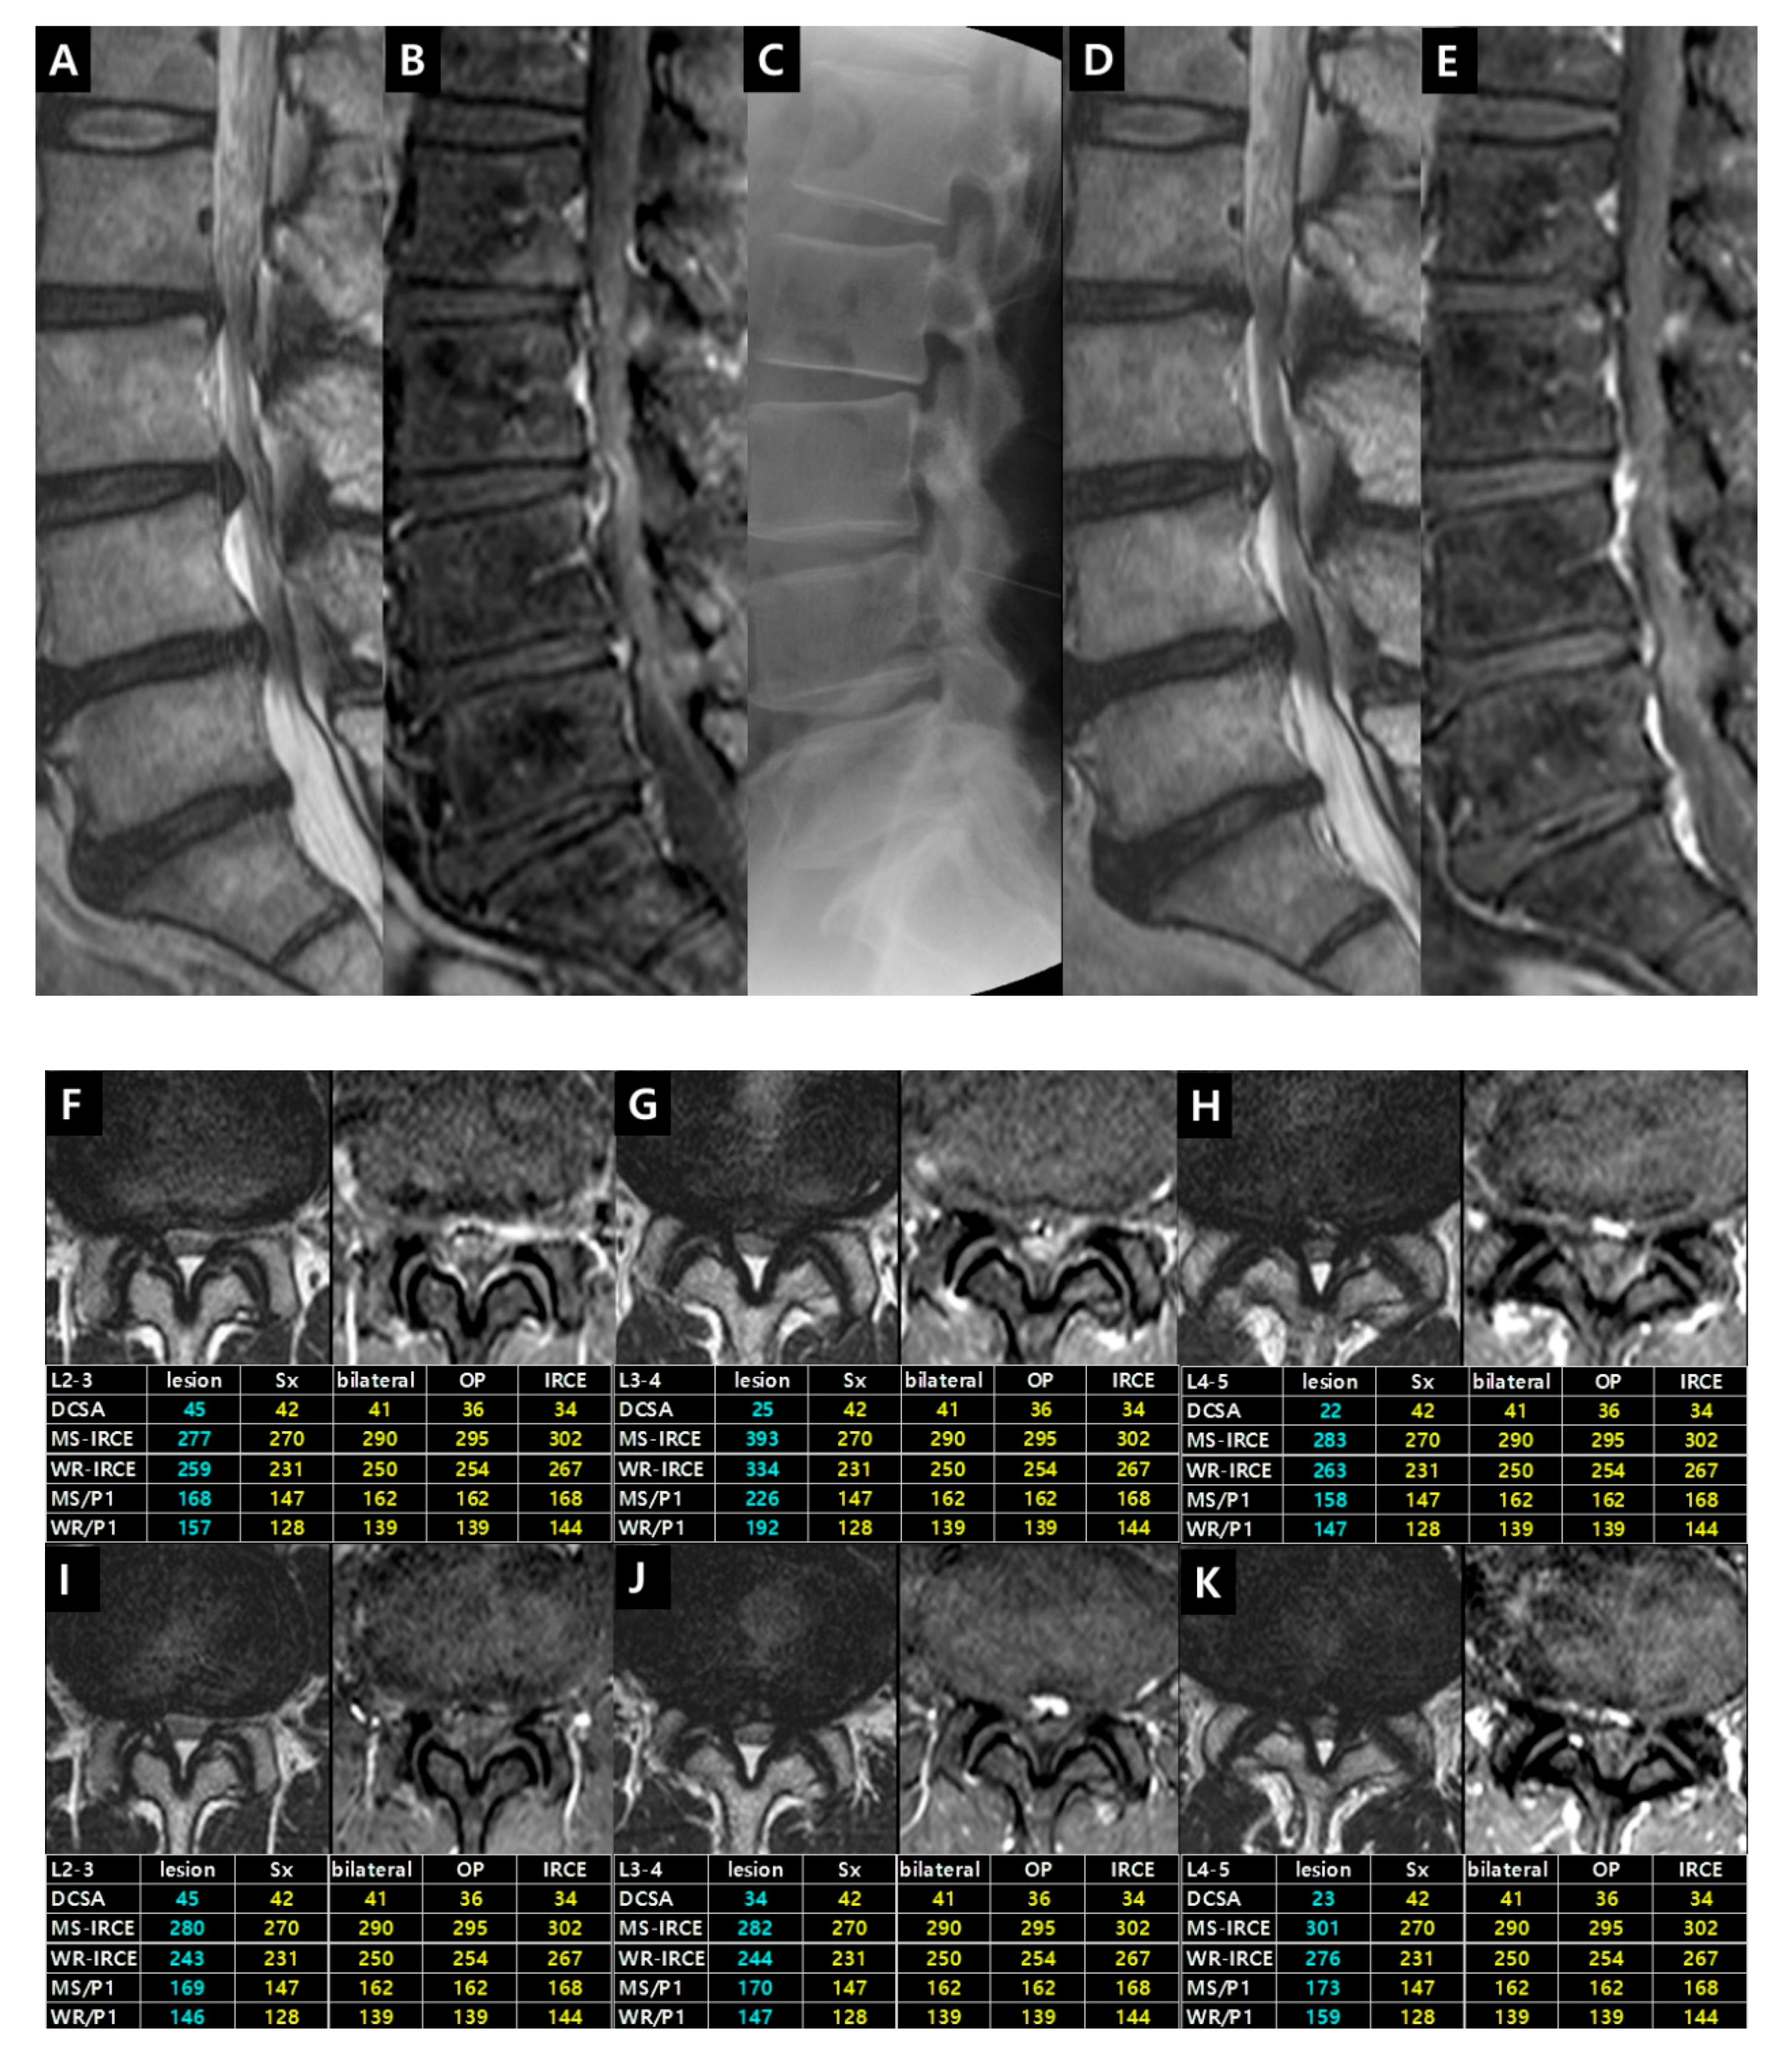

Case 1. Patient (male, 52 years) had complained of bilateral buttock and posterior leg pain for three months. Neurogenic intermittent claudication was evident after 5 min of walking. This case demonstrated the selection of symptomatic level and the reversibilty of IRCE after epidural steroid injection (Figure 9).

Figure 9. Illustrative Case 1. (A) T2-weighted and (B) fat-suppressed enhanced T1-weighted sagittal images showed L2–3, L3–4 and L4–5 central stenosis. (C) An interlaminar epidural steroid injection was performed at L3–4 level. The pain has disappeared for two years. Follow-up MR imaging was taken due to the new development of paresthesia in the left lateral thigh. Follow-up T2-weighted (D) and fat-suppressed enhanced T1-weighted (E) sagittal images demonstrated the disappearance of IRCE on L3–4 level and the appearance of IRCE on L4–5 level. The disappearance of pain and IRCE on L3–4 level after intervention is likely to be caused by a partial absorption of the protruded central disc (the increase of DCSA). T2-weighted and fat-suppressed enhanced T1-weighted axial images on L2–3 (F), L3–4 (G), and L4–5 (H) illustrated the definite visible IRCE with higher IRCE parameters on L3–4 level than L2–3 and L4–5 level. Follow-up images on L2–3 (I), L3–4 (J), and L4–5 (K) revealed no change on L2–3 level, the disappearance of IRCE on L3–4 level, and the increased IRCE parameters on L4–5 level compared with previous images. Changes in enhancement parameters could explain that the symptomatic level changed from L3–4 to L4–5 level. Epidural steroid injection was performed on L4–5 level. The patient has improved.